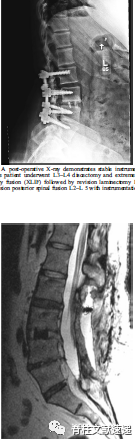

图注:40岁女性,既往多次腰椎手术史,再行翻修手术中发现发现硬膜缺损并给予修复。术后三周,病人出现进行性头痛。腰椎磁共振成像显示术区积液。再次手术探查,但未见渗漏。患者头痛持续,术后24小时进行CT扫描,显示右侧硬脑膜下血肿(SDH),中线移位。病人接受紧急颅骨切开引流减压。随访CT显示SDH恢复良好。